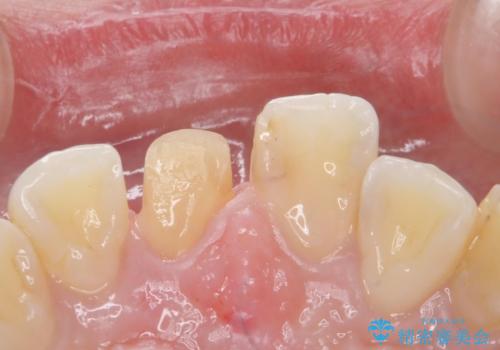

- 前歯のかぶせ物の色が気になるとのことで来院された患者様です。

セラミッククラウンで作り変えていきます。

- 右上1: 仮歯/11,000円、ジルコニアクラウン(スタンダード)/121,000円 合計132,000円(税込)費用は治療当時の料金となります